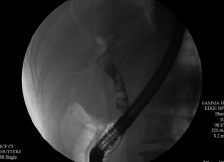

Endoscopic retrograde cholan gio pancreatography (ERCP) was undertaken with the Olympus America Inc. TJF-Q180V duodenoscope and the Olympus America Inc. CleverCut KD-V431Q-0720 triple-lumen papillotome with 0.025-in VisiGlide guidewire. The ampulla and papilla were normal in appearance. The cholangiogram showed smooth stenosis in the mid-CBD, with multiple stones in the common hepatic duct (CHD) and proximal CBD (Figure 2).

Figure 2. Cholangiogram showing multiple stones in the common hepatic and common bile ducts.

Photo courtesy of Allan P. Weston, MD, FACG.